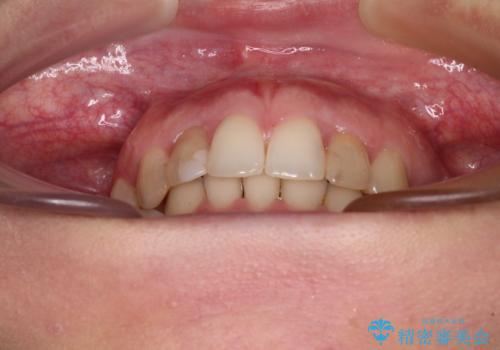

- 前歯の歯並びと神経を取って変色してしまった前歯を気にして来院された患者様です。

上下前歯の歯列不正はインビザラインにより整え、その後に、前歯2本をオールセラミッククラウンにて補綴治療することとしました。